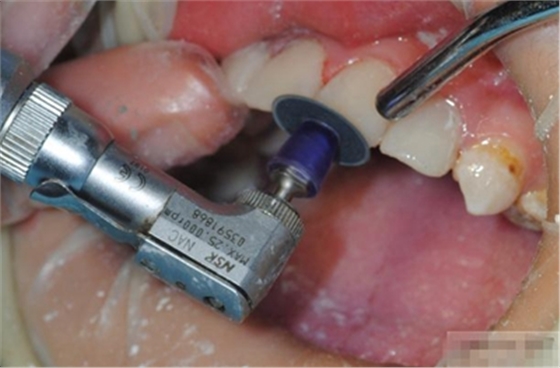

最先選擇最粗的拋光碟去除多余的充填物 建立最初的解剖形態(tài). 10,000 rpm

更換下一個(gè)拋光碟時(shí)要沖洗并吹干牙齒表面

使用中粗的拋光碟進(jìn)一步修整外形,建立邊緣脊和切邊. 10,000 rpm

更換下一個(gè)拋光碟時(shí)要沖洗并吹干牙齒表面.

選擇細(xì)的拋光碟進(jìn)行更進(jìn)一步的表面處理,并為最后的拋光準(zhǔn)備

用超細(xì)拋光碟進(jìn)行最終的拋光,最后完成的表面非常光潔,并且能夠保持很久。

30,000 rpm